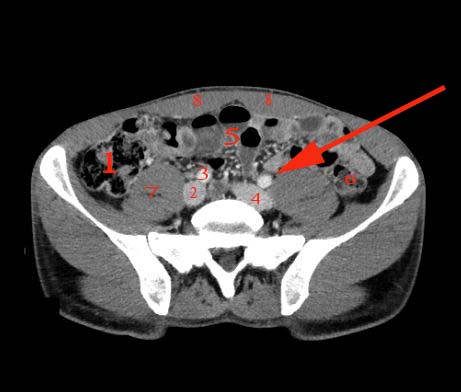

Abdomen axial IQ Test